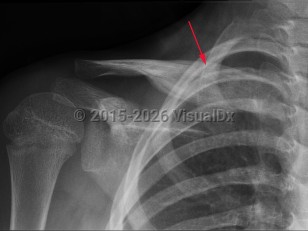

Chronic recurrent multifocal osteomyelitis

Chronic recurrent multifocal osteomyelitis (CRMO) is a rare nonbacterial cause of osteomyelitis. It is an autoimmune inflammatory disorder that causes multi-site, relapsing bone inflammation in the absence of typical infectious causes. Patients present with bone pain, swelling, and decreased mobility. CRMO most often occurs in children. CRMO sometimes co-exists with other autoimmune diseases such as inflammatory bowel disease or within a genetic syndrome. Nonsteroidal anti-inflammatory drugs (NSAIDs), corticosteroids, and bisphosphonates have all been used to treat CRMO. The disease typically has a relapsing and remitting course.